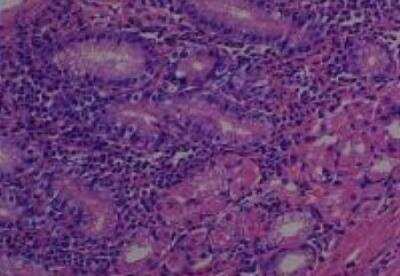

Hematoxylin & Eosin Stain: Human Common Tissue MicroArray (Normal Adjacent) [NBP2-30215] - 103. Stomach